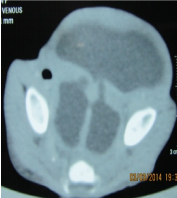

Investigations revealed anaemia, leucocytosis, deranged electrolytes and metabolic acidosis. USG was suggestive of a suspicious obturator hernia on right side. CT scan was suggestive of bulging of a large complex cystic structure with air-fluid level on the right side. Sagittal reformations also suggested the inferior descent of the cystic structure through the perineal floor (Figures 4 &5). The deranged laboratory parameters were corrected and the child was taken for emergency exploration. Intra-operatively, it was found that the massive hydrocolpos was protruding through the perineum as the bulge. There was no perineal or obturator defect. Drainage of the massive hydrocolpos was done by an abdominal vaginostomy (Figures 6&7).

Figure 4 Axial scan at the level of perineum s/o bulging of the fluid filled structure on the right side.